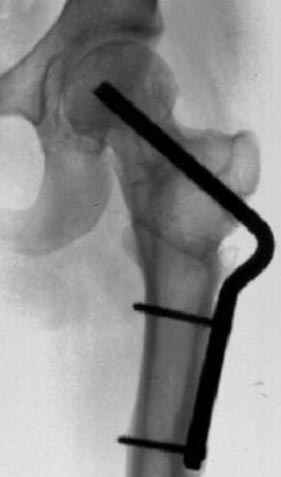

5:24 Рентгенограмма таза, вызывают врача ортопеда (снимок N1), его диагноз: закрытый переломо-вывих правого тазабедренного сустава, получает добро на закрытую репозицию в приемном отделении

N 2

7:30 начало операции, больной на спине, попытка репозиции после анестезии N3, укладка больного на боку, доступ Kocher- Langenbeck, состояние седалищнего нерва около 2.5см кровоподтек, через joistick головка бедра приподнята, освобовождение сустава, фрагмент заднего края более 3х4 см репонирован на свое место. После промывания

сустава, репозиция вывиха (N4), фиксация фрагмента 2.7(4) мм шурупами и допольнительно реконструктивной пластиной на 8 дырок, фиксация 3.5мм шурупами проксимально и дистально.

Интраоперционные N5 косая запирательная и N6 подвздошный снимок